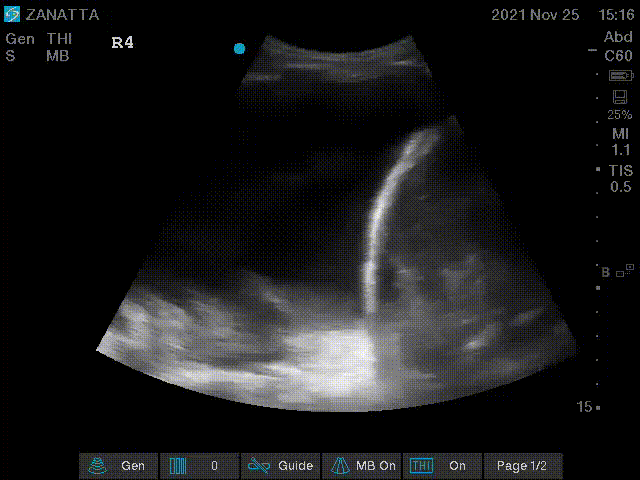

You move on to the parasternal long and short axis views.

Parasternal Long Axis